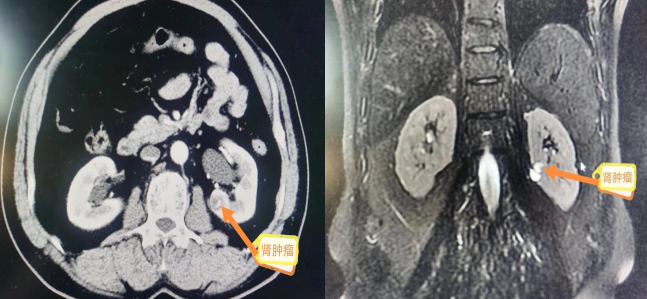

患者为男性,60岁,山西人,在呼和浩特市打工,因“体检发现肾肿瘤,增强CT考虑恶性”就诊。因肿瘤位置比较特殊,位于肾脏后唇,靠近肾门,且肿瘤直径小于4cm,按照诊疗原则行“保肾”手术——肾部分切除术,但因肿瘤位置特殊(肾脏后唇靠近肾门),一般为安全保险起见均行根治性切除术,患者听闻马可为院长手术技术高超,放弃回山西老家治疗,特慕名前来我院求诊,要求行“保肾”手术治疗。

马可为院长主持科内进行术前讨论,白少雄主任医师、温宇红主任医师、武强管床医师参与讨论,马可为院长总结:该患者肿瘤核磁影像学T分期为T1a,肿瘤位于肾脏特殊部位(肾门),决定先行后腹腔镜下肾部分切除术,如遇术中难度大,可改为后腹腔镜下根治性肾切除术或开放式肾(部分)切除术。经与患方沟通,患者及家属表示接受此方案。